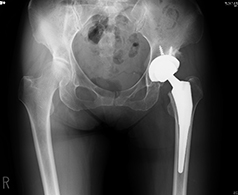

人工股関節全置換術(THA)

人工股関節全置換術とは、すり減った軟骨と痛んだ骨を取り除き、金属やプラスチックでできた人工の関節に置き換える手術です。

痛みの原因を除去できるため、確実な除痛効果が得られます。長期的にも、人工股関節全置換術施行後、10年で再置換術が必要となる確率は5%以下であり、多くの方が10年後も良好な機能を保ちつつ生活されております。

当院では、変形の程度によりますが、最小侵襲手術手技を採用し、かつ長期的な成績改善を第一優先として正確なインプラント設置を行っております。術直後の痛みは、麻酔科の協力により良好にコントロールされます。リハビリは術翌日より開始し、日常生活の復帰や社会復帰へ向け準備致します。主な術後合併症である感染と脱臼の発生率は、一般に約1-2%と5%前後ですが、当院では現在筋肉を切らない手術(MIS)を採用しており、その率は非常に低く抑えられています。

当院で行っている最小侵襲手術(MIS)

従来、人工股関節全置換術は、15cm~20cmの皮膚切開を要し、筋肉を切開して関節に達しておりました。近年、手術手技や手術機械の飛躍的な進歩によりMIS手術が導入され、10cm~12cmの皮膚切開で、かつ筋肉同士の間からアプローチするため筋肉をほぼ切らずに従来と同等の人工股関節置換術が可能となりました。当院では十分にトレーニングを積んだ専門医が適応を十分に判断した上で、積極的にMIS手術を取り入れており、術後早期の回復及び脱臼率の低下などの成果が上がっています。